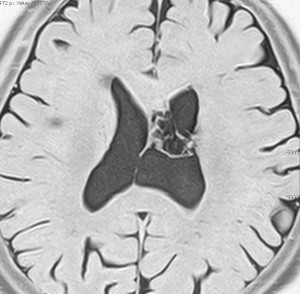

無症状で偶然発見された38歳女性の症例

central neurocytomaが透明中隔 septum pellucidum から発生していることがよくわかる症例です。症状はありませんでしたが,この腫瘍がこのままのサイズで留まることはあり得ないので手術摘出を勧めました。これ以上大きくなると手術にしても放射線治療にしてもリスクが大きくなりすぎます。脳弓にくっつくので脳弓損傷を避けるのが手術のポイントです。脳室壁にくっつくのですが剥がしていけば取れますが,大きな上衣下静脈 large subependymal vein の損傷には注意を払います。

手術後の画像です。脳神経外科の先生は手術根 surgical track に注目して下さい,左頭頂葉皮質切開 transcortical approachで手術を行っています。このルートでは全く手術後の神経脱落症状が出ませんでした。central neurocytomaの手術方法は,上記に加えて前頭葉皮質切開でまっすぐ前角に入る方法と経脳梁法 transcallosal approachがあります。経脳梁法は限られた小さめの腫瘍にしか応用できません。anterior callosal approach以外ではdisconnection syndromeが出るからです。central neurocytomaは脳室の壁にベトベトくっつくし,anterior callosal approachでは脳室壁の観察はかなり限られるからです。大きなものでは必ず経皮質法を選択して下さい。